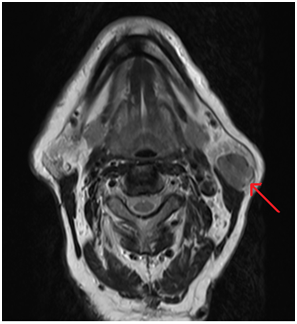

Five years later, the patient presented with a metachronous lesion overlying the left parotid gland. Ultrasound guided fine needle aspiration again, was suggestive of Warthins tumour. A T2-weighted MRI scan showed evidence of a 2.5cm well defined lesion within the left superficial parotid tissue (Figure 2). The patient underwent another superficial parotidectomy using the same surgical approach (Figure 3). Histopathological findings of the specimen were classical for Warthins tumour, showing papillary finger-like processess of columnar epithelium, eosinophillic uptake of dye and lymphoid aggregates with germinal centre formation (Figure 4). Following surgery, the patient suffered with transient Grade 2 left sided facial weakness (as per House Brakeman Classification) olasting approximately 3weeks and permanent numbness of the left ear lobe. The patient was subsequently discharged from clinic after 3months.

Figure 2 Axial slice of an MRI at the level of the parotid gland showing a 2.5cm well defined lesion in the superficial part of the left parotid gland.